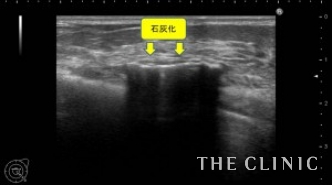

この方は、20年前に大胸筋下へバッグを挿入されています。今回、乳がん検診にてバッグの破損と被膜の石灰化を指摘され、バッグ抜去をご希望でご来院されました。エコーにて、両側のバッグ破損と被膜の石灰化を認めます。右側は脇の近くまでシリコンが漏れ出ている状態でした。

バッグ抜去後のエコー画像です。石灰化した被膜は、バッグを取り出すのが困難になり抜去したあとも石灰化が消えることはありません。